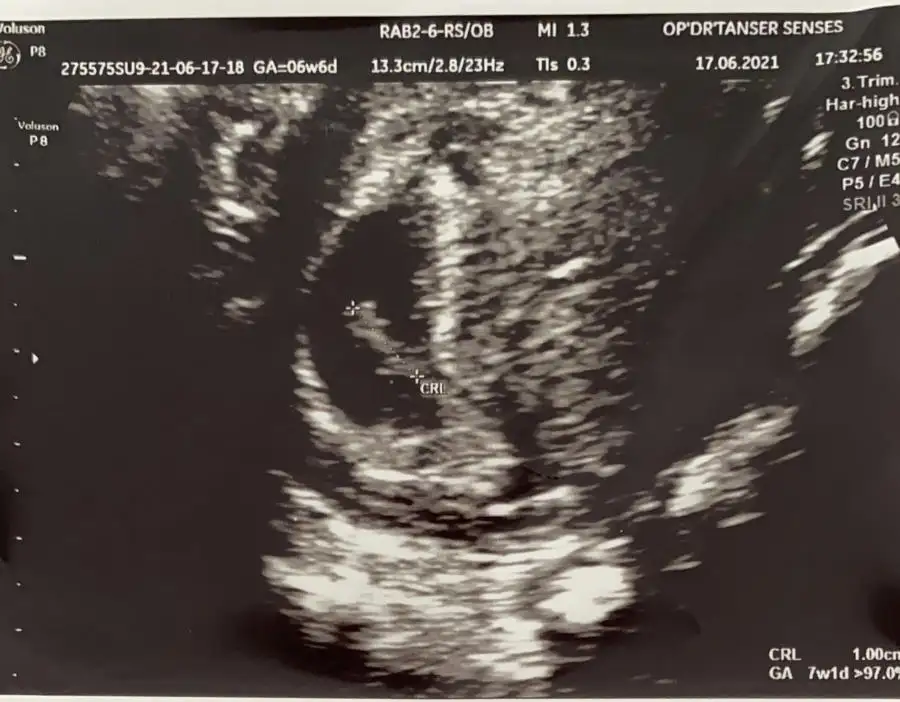

Canim tam 8 haftalik, vajinal ultrasonla bakti. Sagdan yumurtlamissin dedi, kalp atisi 153 cikti. Cinsiyet tahminin var mi ☺️ Bir de 6 haftalikken fotosunu da ekledim, o da vajinal muayeneydi.

Eklentiler

• C9AB79D5-49DE-4AF8-955D-4B4FD4770913.webp

C9AB79D5-49DE-4AF8-955D-4B4FD4770913.webp

32,3 KB · Görüntüleme: 106

• 1CDBD389-34B9-4996-851A-09602A972C10.webp

1CDBD389-34B9-4996-851A-09602A972C10.webp

5 KB · Görüntüleme: 95